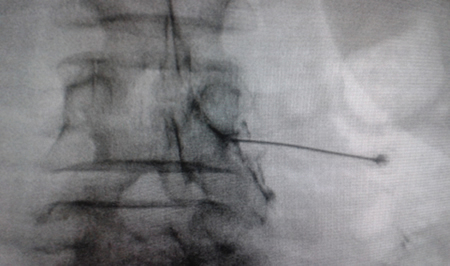

Figure 1

Figure 2